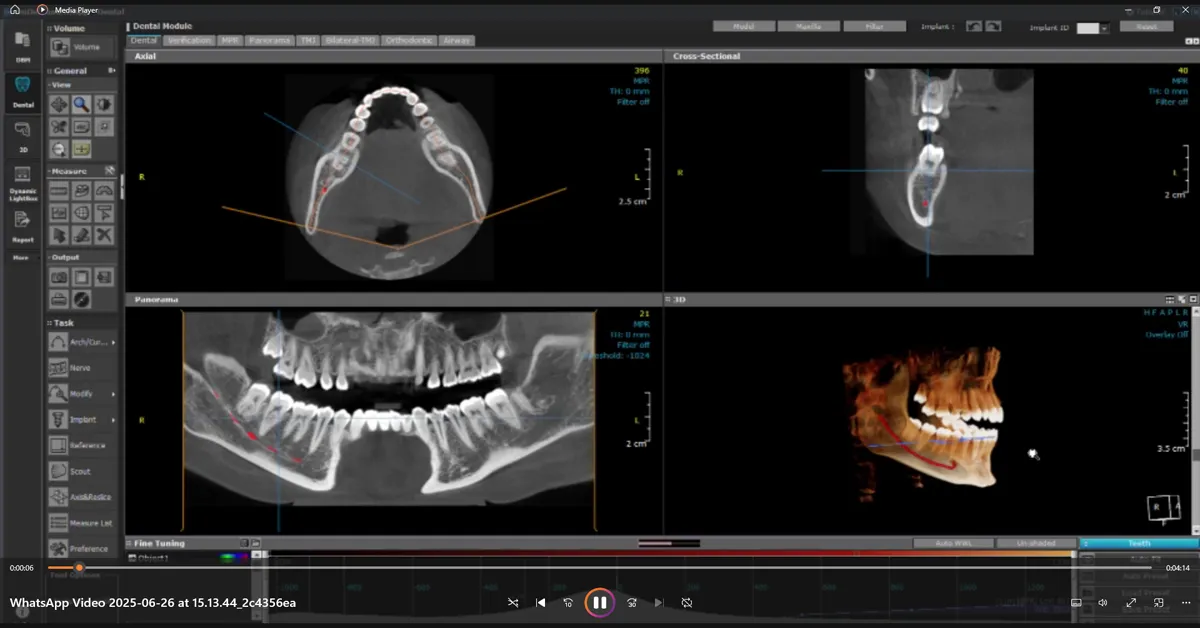

1) Preparation and planning:

We took clinical photos and CBCT 3D scans to study the gum shape and bone. The team planned where to harvest graft tissue and how the implant and crown would sit for the best long‑term outcome.